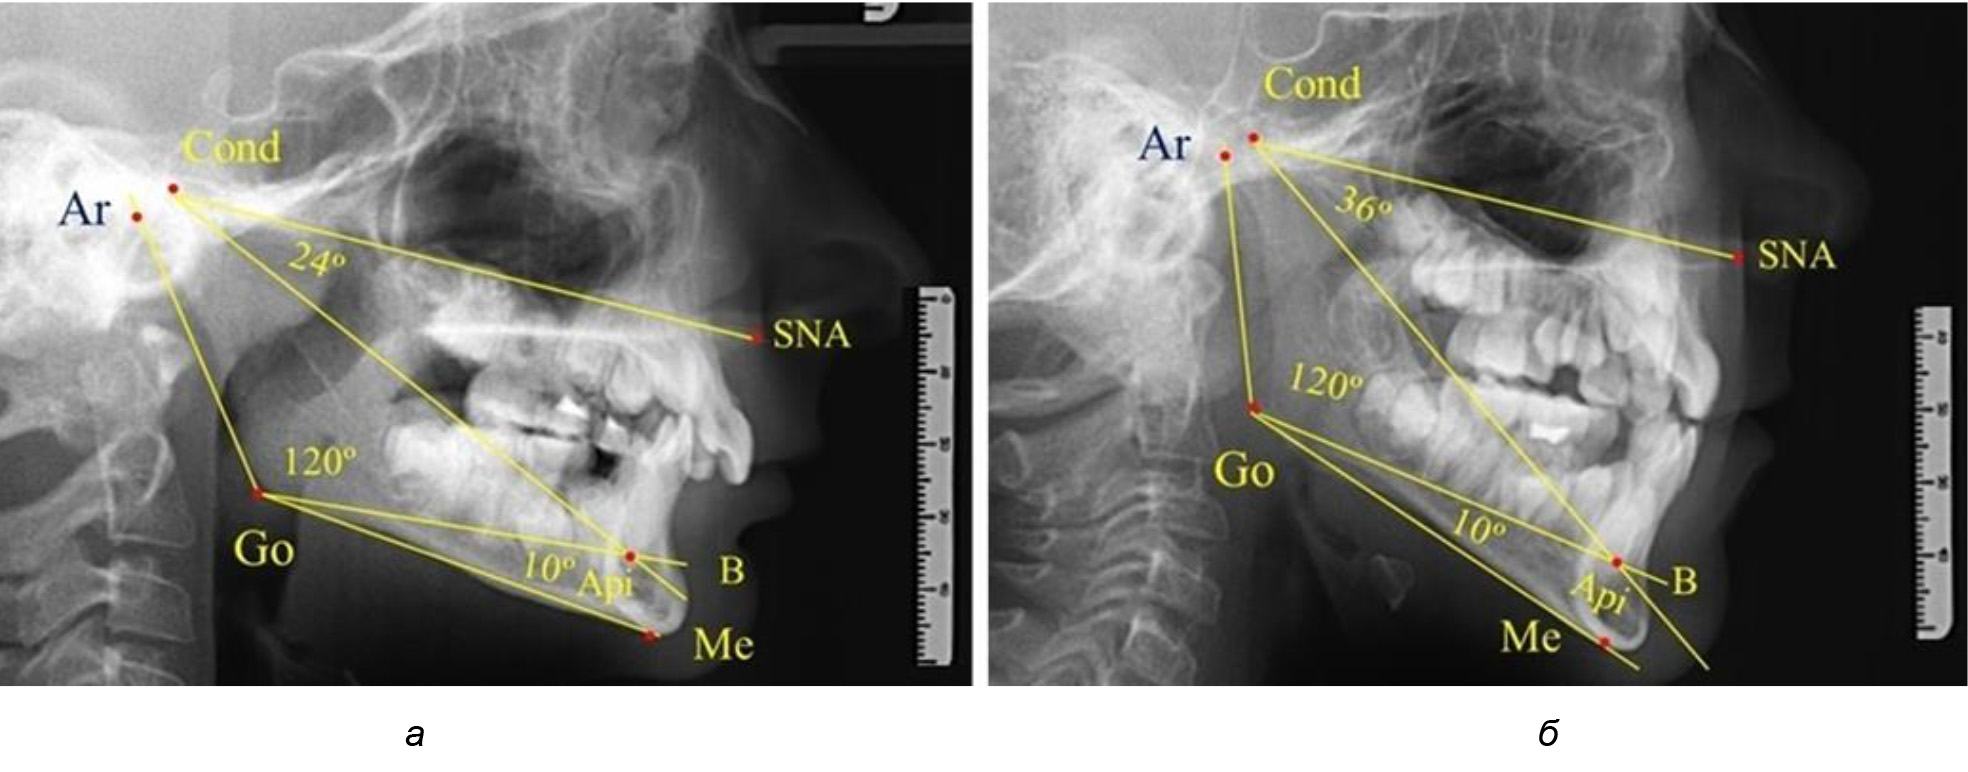

При анализе ТРГ 5 детей в периоде прикуса молочных зубов отмечено, что величина основного угла гнатической части лица SNA-Cond-Api, как правило, в норме составляла около 30°, и его величина была относительно стабильной у всех обследованных детей. В то же время угол нижней челюсти и его составляющие отличались вариабельностью параметров при различных показателях нижнечелюстного угла (рис. 4).

Рис. 4. Особенности ТРГ (а) и 3D-модели (б) в периоде прикуса молочных зубов

Таким образом, в периоде молочного прикуса с оптимальными окклюзионными соотношениями, несмотря на линейные размеры в вертикальном и сагиттальном направлении, которые, безусловно, меньше параметров взрослых людей, величина основного угла гнатической части лица SNA-Cond-Api соответствовала параметрам людей с полностью сформированным физиологическим прикусом постоянных зубов. Анализируя данные рентгенограмм детей в периоде сменного прикуса, отмечено, что величина основного угла гнатической части лица SNA-Cond-Api, так же как в молочном и постоянном прикусе, в норме составляла от 28 до 32°. В то же время угол нижней челюсти и его составляющие отличались вариабельностью параметров при различных показателях нижнечелюстного угла. Достоверных различий угла гнатической части после смены нижних медиальных резцов и прорезывания первых постоянных моляров (4 ребенка) не было; происходил очередной этап подъема высоты прикуса и увеличение линейных размеров костей гнатической части, однако угловые параметры были относительно стабильны. После смены всех резцов и замены первых молочных моляров первыми премолярами (6 человек) увеличивались линейные размеры при сохранившихся угловых показателях гнатической части лица (рис. 5).

Рис. 5. Варианты ТРГ после прорезывания ППМ и нижних резцов (а), всех резцов и первых премоляров (б)